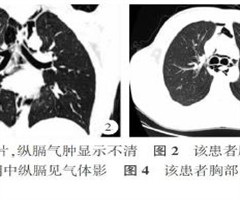

青少年自发性纵隔气肿影像学表现与临床分析

【摘要】目的目的 探讨青少年自发性纵隔气肿(SPM)的影像学表现与临床分析。方法回顾性分析31例临床明确诊断的青少年SPM患者为本次的研究对象。患者均接受数字X线摄影(DR)或/和多排螺旋CT影像学检查,重点分析影像学结果和患者临床特点。结...